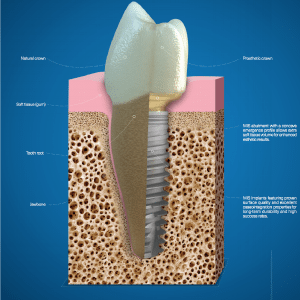

A dental implant is basically an artificial tooth root (typically made from titanium) that is anchored in place of a missing tooth. A temporary protective cover screw is placed on the implant while it fuses with the jawbone (a process called osseointegration). This process can take up to six months to complete, but creates an incredibly stable, durable prosthetic. After completed osseointegration, the protective cover is replaced by a temporary crown. This serves as a template around which the gum grows and shapes itself in a natural way. The process is completed when the temporary crown is replaced by a permanent crown.